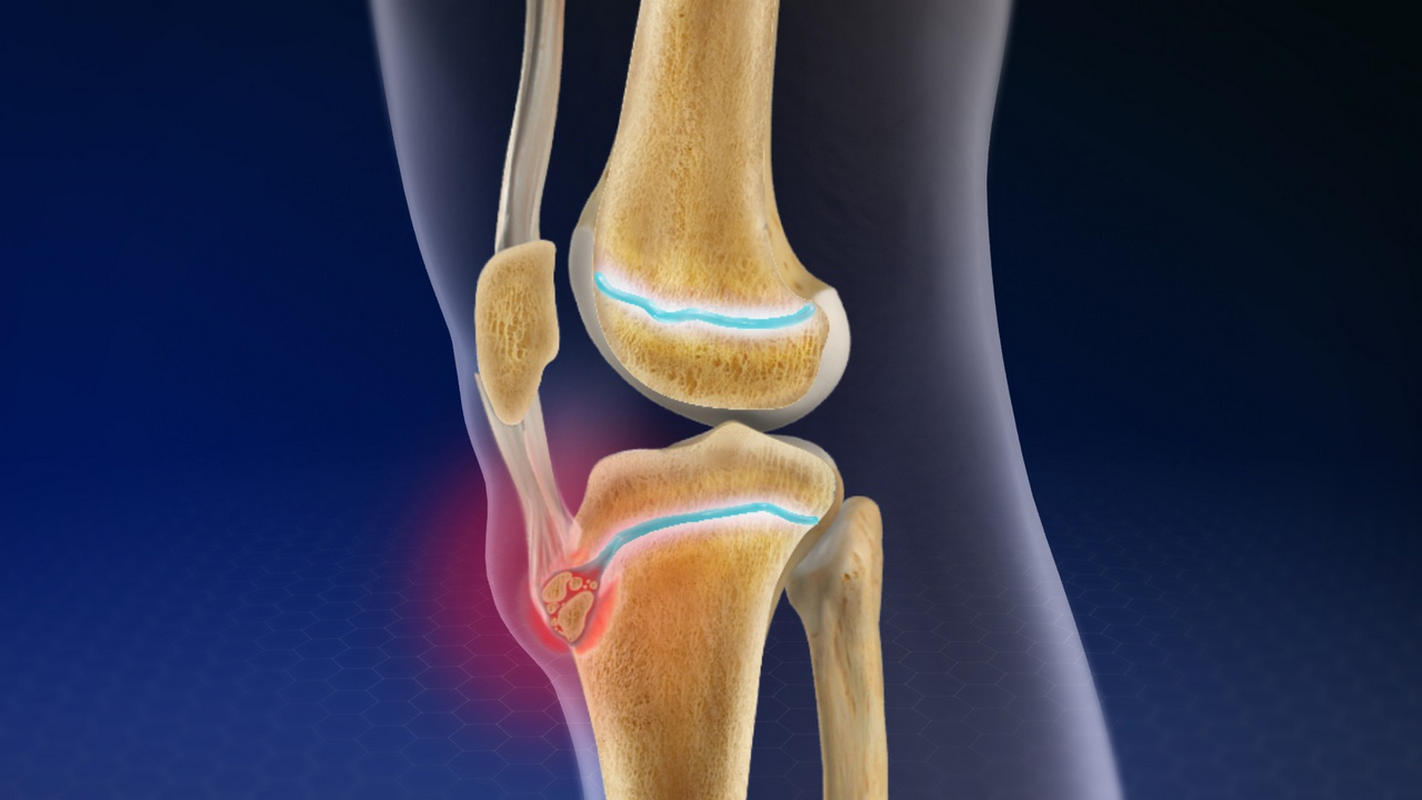

Η πάθηση εντοπίζεται στο σημείο όπου ο επιγονατιδικός τένοντας καταφύεται στο κνημιαίο κύρτωμα, δηλαδή στη μπροστινή οστική προεξοχή της κνήμης κάτω από την επιγονατίδα.

Κατά την ηλικία των 10 έως 15 ετών, το κνημιαίο κύρτωμα δεν έχει ολοκληρώσει την οστική του ωρίμανση και παραμένει ευάλωτο σε μηχανικές καταπονήσεις. Ο τετρακέφαλος μυς του μηρού, μέσω του επιγονατιδικού τένοντα, ασκεί επαναλαμβανόμενη έλξη στο σημείο αυτό, ιδιαίτερα κατά το τρέξιμο, τα άλματα και τις απότομες επιταχύνσεις.

Η συνεχής καταπόνηση μπορεί να οδηγήσει σε φλεγμονή, μικροτραυματισμούς ή ακόμη και σε μικρές αποσπάσεις οστικού ιστού, προκαλώντας πόνο και τοπική ευαισθησία.